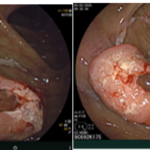

Ca lâm sàng: Ung thư đại tràng ở bệnh nhân 15 tuổi

GS.TS Mai Trọng Khoa; BSNT Hoàng Mạnh Đức, Ths Bùi Quang Lộc , PGS.TS Phạm Cẩm Phương, Bsck II Hoàng Anh, Trung tâm y học hạt nhân và...